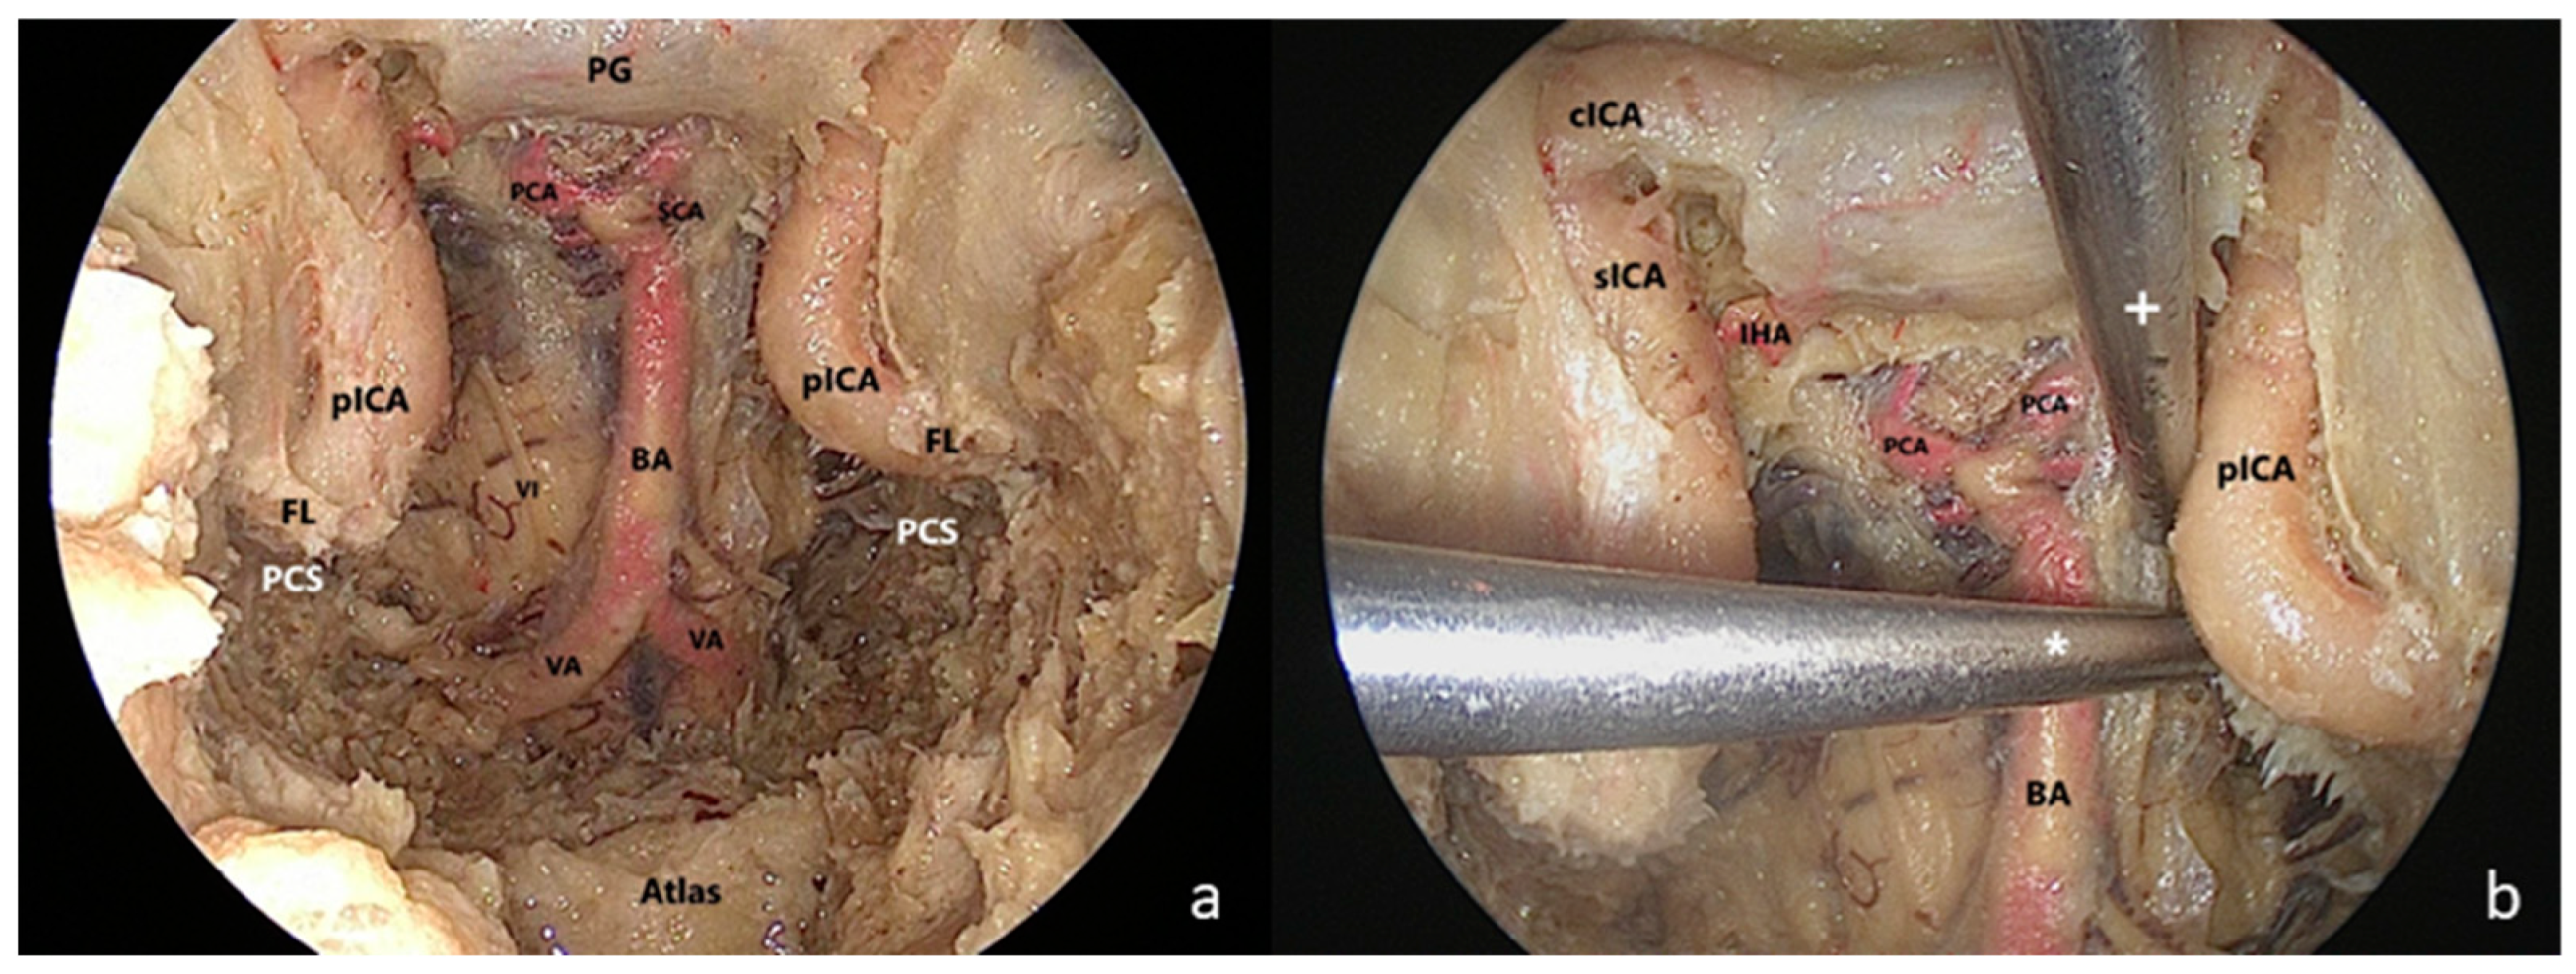

A “two-surgeon four–hand technique” was adopted. The medial PA was drilled up to the clival dura medially, the foramen lacerum (FL) inferiorly, the pcICA antero-laterally, the petrous bone postero-laterally and the cavernous sinus superiorly. The ‘carotid-clival window’ was opened, providing access to the PCS [18]. The clival dura was incised along the midline in a T shape for identifying intradural landmarks (Figure 4).

Figure 4.

Endoscopic endonsal transsphenoidal approach with extended exposure of the ventral skull base. (a) The clivus was completely drilled out and the paraclival segment of the internal carotid artery (pcICA) was exposed bilaterally. The medial petrous apex was drilled up to the foramen lacerum (FL) inferiorly, providing access to the petroclival synchondrosis (PCS). The clival dura was then removed to identify intradural landmarks. (b) Two straight surgical aspirators were inserted through the endonasal (+) and transmaxillary (*) corridor showing the different angles of attack toward the PCS; BA: basilar artery; FL: foramen lacerum; PCA: posterior cerebral artery; PCS: petroclival synchondrosis; PG: pituitary gland; pICA: paraclival segment of the internal carotid artery; SCA: superior cerebellar artery; VA: vertebral artery; VI: sixth cranial nerve.